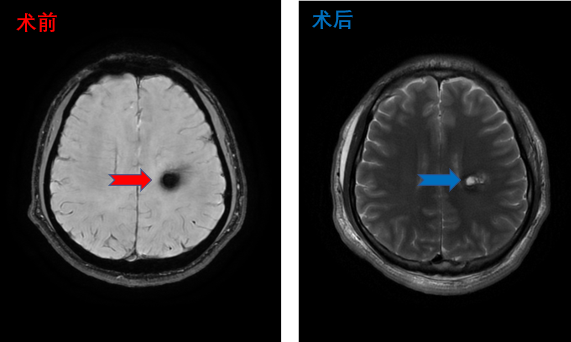

丘脑海绵状血管瘤患者影像,术后患者四肢活动正常